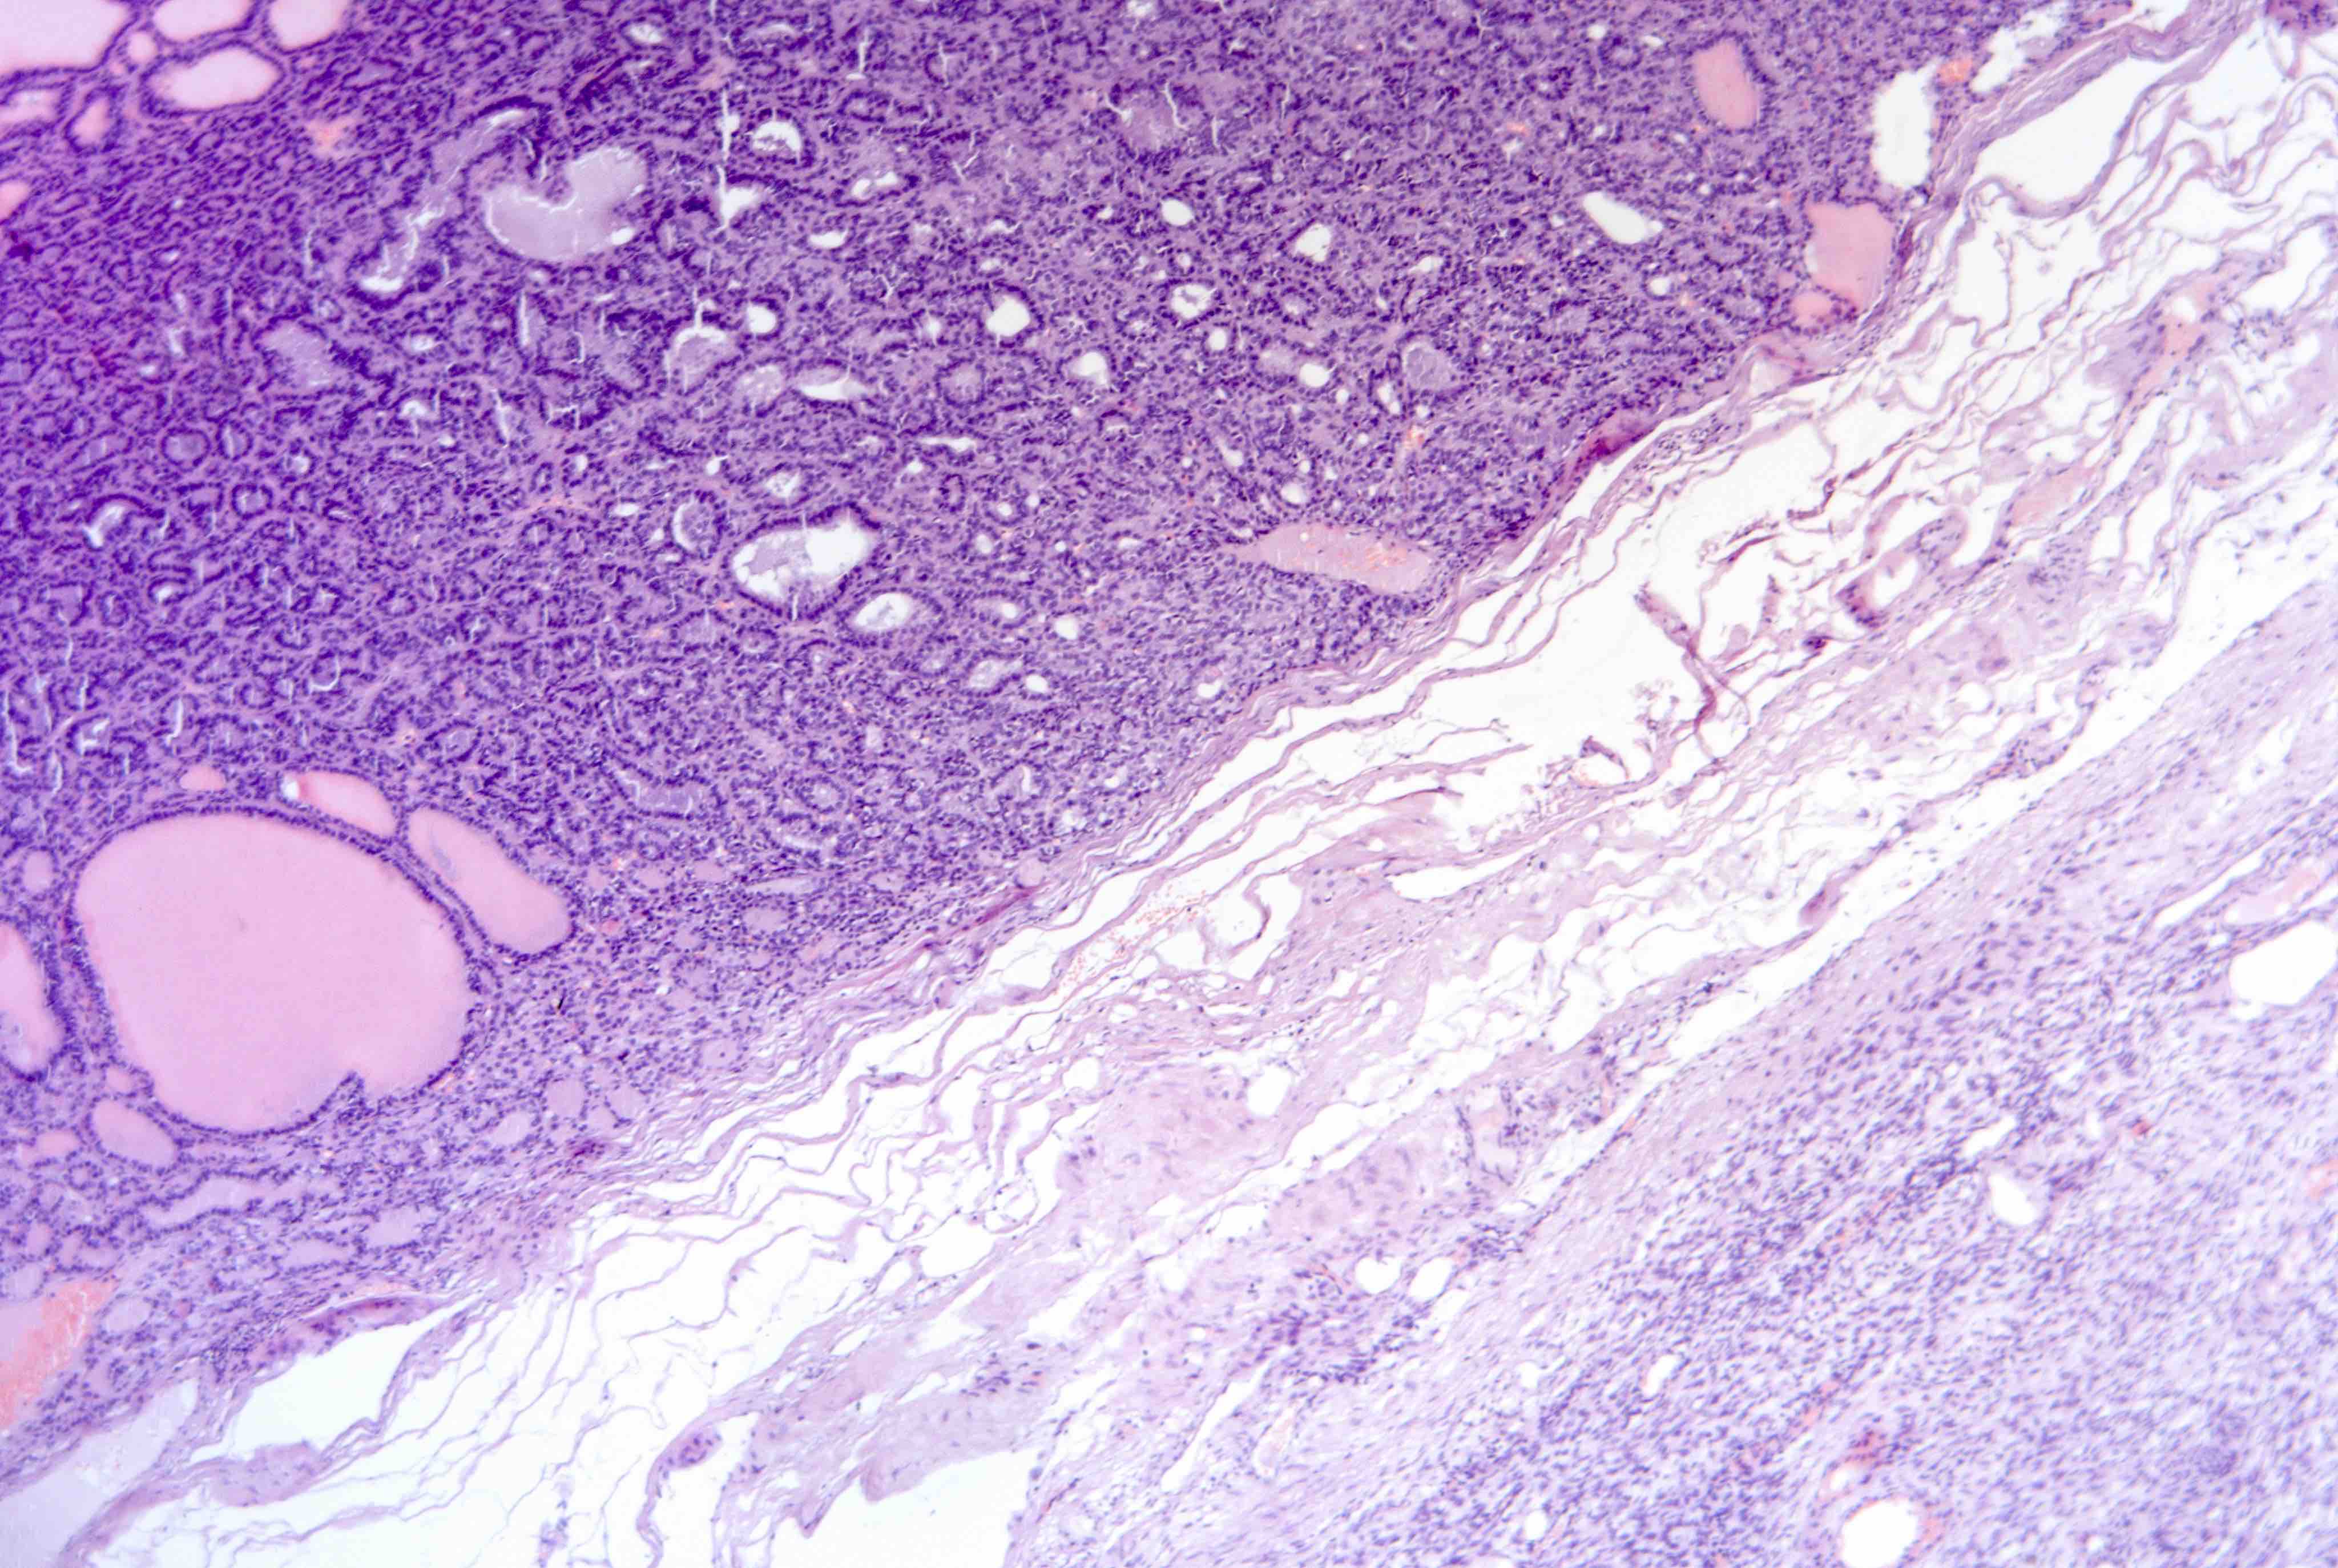

Microscopic (histologic) description

- Mixture of mature, benign tissues

- Ectodermal (most common): squamous epithelium, sebaceous glands, hair follicles, brain tissue

- Mesodermal (second most common): bone, cartilage, smooth muscle, fibroadipose tissue

- Endodermal: intestinal or respiratory epithelium, thyroid, salivary gland

- Microscopic foci of immature neuroepithelium (less than or equal to 4 foci or 21 mm2) does not warrant diagnosis of immature teratoma and will not affect prognosis (Int J Gynecol Pathol 1987;6:203)

Microscopic (histologic) images